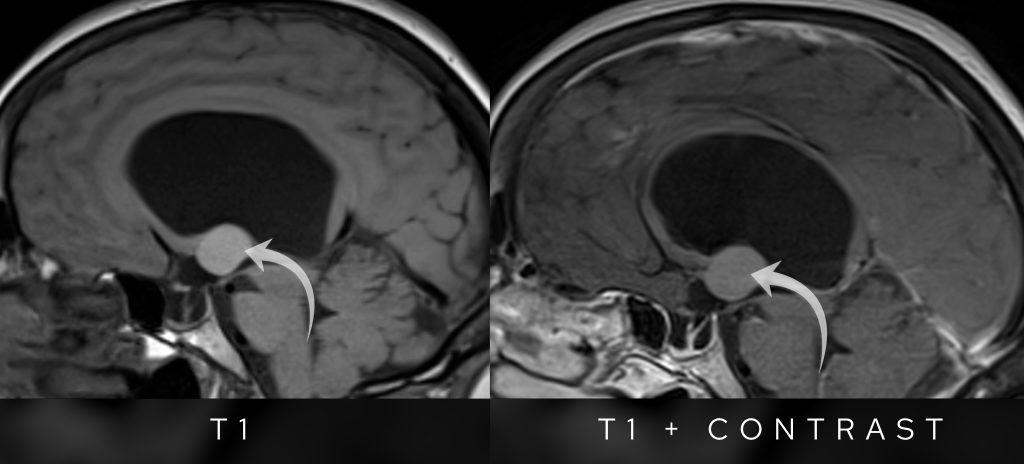

- T1-weighted: It appears brighter than the surrounding brain tissue.

- Post-contrast images: There is no significant enhancement, ruling out highly vascular lesions.

T1 pre and post contrast sagittal images show no appreciable enhancement in the lesion post intravenous gadolinium contrast.